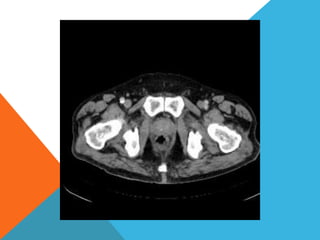

El paciente presentó síntomas de sangrado digestivo y pérdida de peso. Exámenes revelaron gastritis crónica asociada a H. pylori. Un tumor fue descubierto en una colonoscopia normal. La cirugía removió un tumor fibroide solitario, una rara neoplasia mesenquimal que usualmente crece lento y tiene bajo potencial de malignidad. El pronóstico después de la remoción quirúrgica es generalmente bueno.